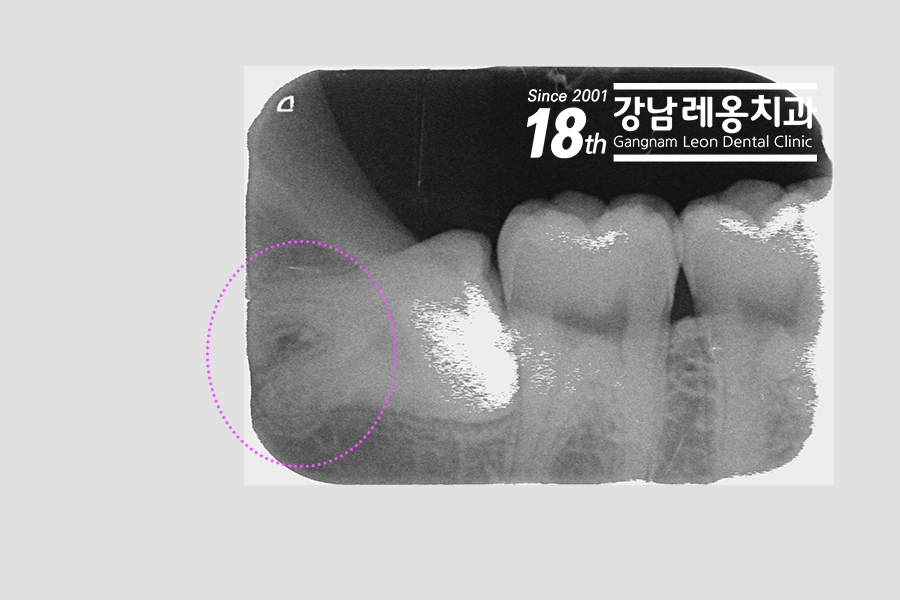

만곡된 치근을 조금 더 자세하게 찍었습니다. 그리고 상, 하악 마취를 진행한 뒤 약이 퍼질 동안 주의할 사항들을 먼저 알려 드렸습니다. 수술이 끝난 후 설명을 하면 정신이 없고 불편해서 중요한 내용들에 집중을 하기가 어렵기 때문에죠^^

수평으로 매복되어 있어서 치관을 분리하여 뽑아 냈습니다. 그러던 중!! 역시나 딱 하는 소리!! 부러진 것이었어요. 그치만 베테랑 원장님은 당황하지 않으시고 파절 된 위치와 크기를 확인하기 위해 엑스레이를 한번 더 찍어보셨어요.

위쪽에 심하게 구부러진 녀석이군요. 이렇게 뽑는 중에 사랑니 뿌리가 파절이 되는 일은 흔합니다. 이에 대처하는 두가지 방법이 있는데, 하나는 그냥 놔두는 거에요. 조각이 매우 작거나(2mm 이하) 신경관과 매우 가까운 경우, 염증을 일으킬 가능성이 희박할 때입니다. 그치만 이번 증례에서 원장님은 남은 조각을 꺼내기로 하셨어요.